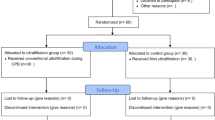

Between May 2021 and September 2022, 53 infants were enrolled following cardiac surgery. The consort diagram is shown in Fig. 1. Declined consent accounted for six infants who were excluded from the analysis and missing ultrasound images accounted for the loss of seven images over the study period. The demographic and clinical characteristics of all infants are shown in Table 1. The median time from surgery to baseline measurements was 26 h [IQR, 23–29]. The median positive end-expiratory pressure (PEEP) at baseline, 24 and 48 h were 5 cmH2O (IQR: 5,6), 5 cmH2O (IQR: 5,6) and 6 cmH2O (IQR: 5,6), respectively. One child was extubated shortly after enrolment, seven on day 2 and nine on day 3.